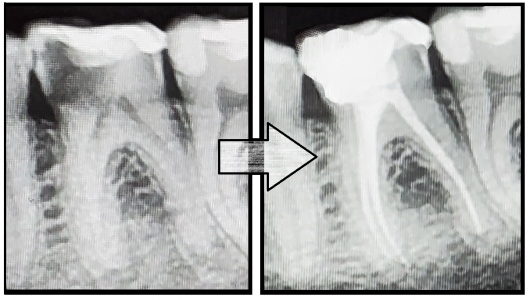

Jestem Amerykaninem, ale mieszkam w Polsce ponad 10 lat. Zajmuję się zachowawczą, leczeniem kanałowym pierwotnym i wtórnym pod mikroskopem, protetyką i prostą chirurgią. Wykonuję też Bonding i Flow Injection Technique.

Endodoncja mikroskopowa

Leczenie endodontyczne